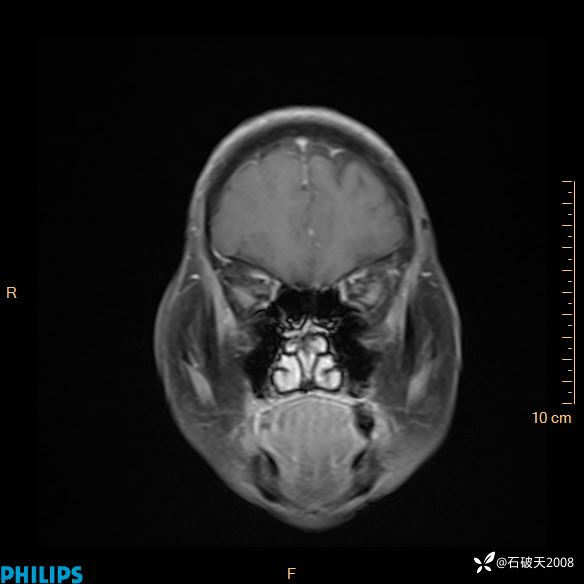

2020.11.14MR

增强冠状位